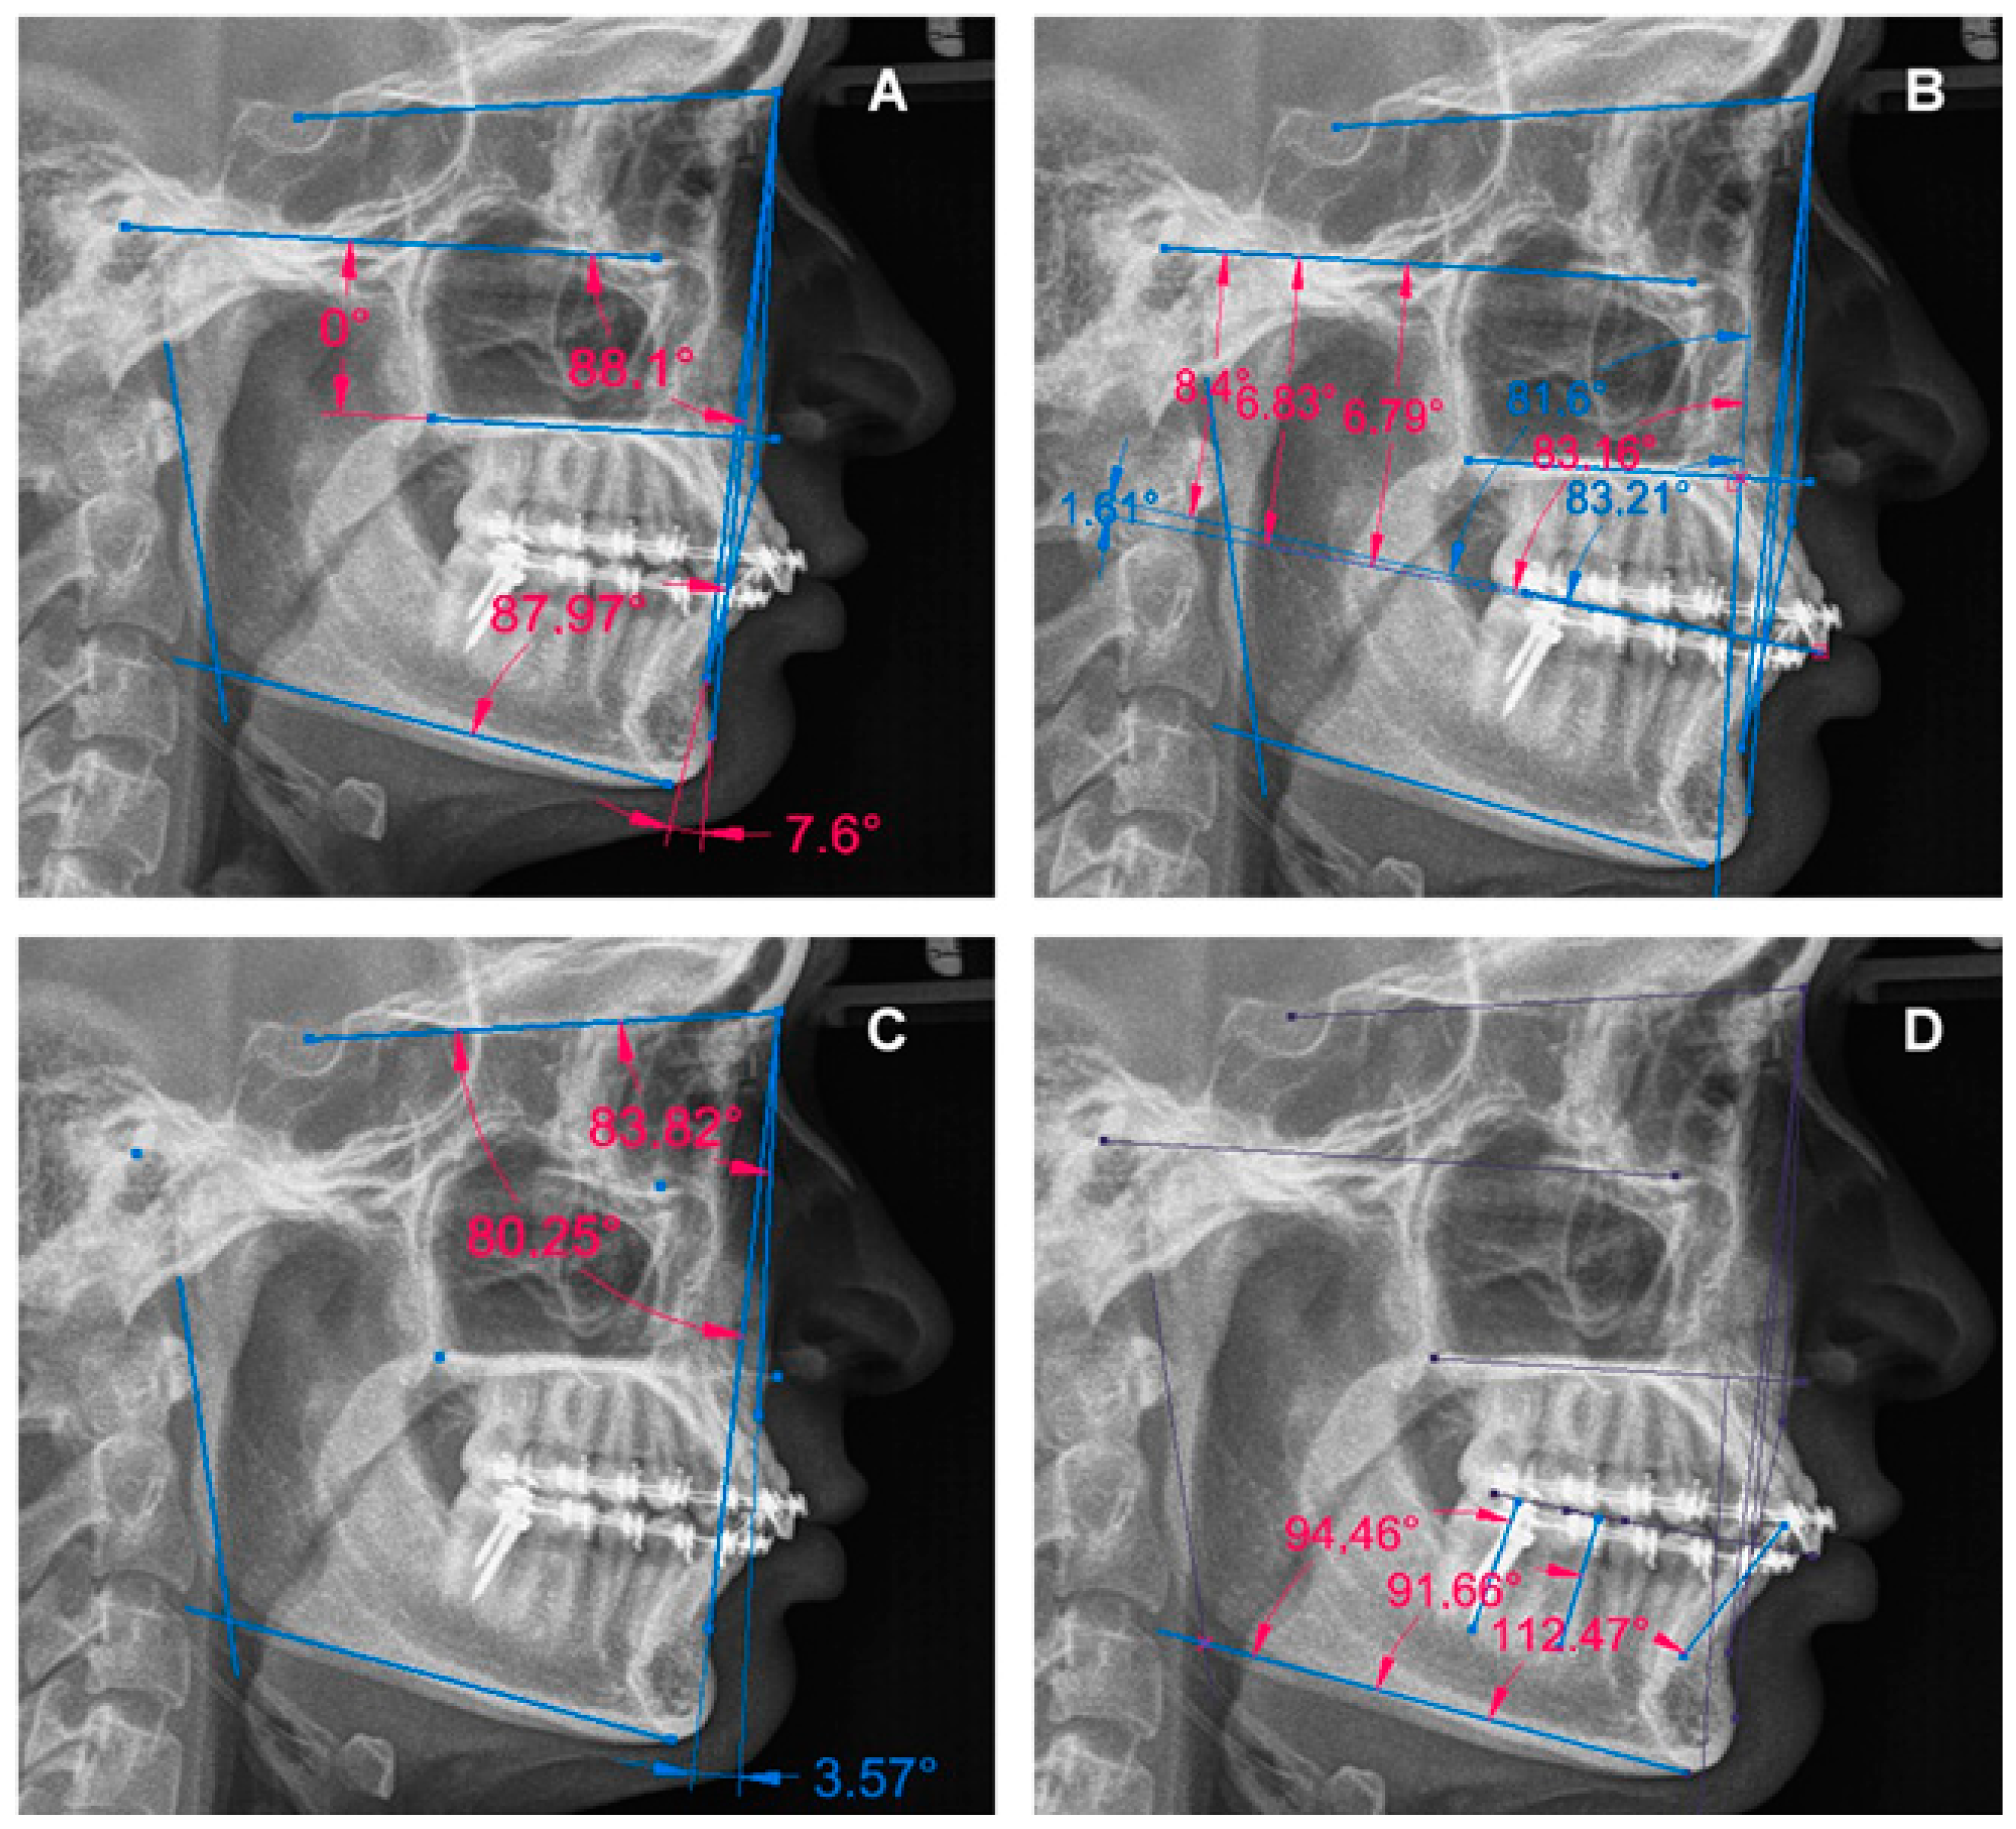

3. Results

3.2. Report of the Specific Characteristics of the Cases

3.2.1. Case 1

3.2.2. Case 2

3.2.3. Case 3

3.2.4. Case 4

3.2.5. Case 5

3.2.6. Case 6

3.2.7. Case 7

3.2.8. Case 8

3.2.9. Case 9

| Case | Skeletal Diagnosis | Distalization Arch | Time | COP | AOP | POP | I | 1M | 2M | SMP | VMP |

|---|---|---|---|---|---|---|---|---|---|---|---|

| 1 | Class I Neutral Angle | Mandible | T1–T2 | Flattened | Tipped | Flattened | Decreased | Increased | Decreased | Not changed | Not changed |

| T2–T3 | Tipped | Tipped | Flattened | Decreased | Decreased | Decreased | Not changed | Not changed | |||

| T1–T3 | Flattened | Tipped | Flattened | Decreased | Decreased | Decreased | Not changed | Not changed | |||

| 2 | Class I Low Angle | Mandible | T1–T2 | Tipped | Tipped | Flattened | Decreased | Decreased | Decreased | Not changed | Not changed |

| T1–T3 | Tipped | Tipped | Flattened | Decreased | Decreased | Decreased | Not changed | Not changed | |||

| 3 | Class II Neutral Angle | Maxilla | T1–T2 | Flattened | Flattened | Flattened | Increased | Decreased | Increased | Not changed | Not changed |

| T2–T3 | Tipped | Tipped | Tipped | Decreased | Decreased | Decreased | Changed | Not changed | |||

| T1–T3 | Tipped | Tipped | Flattened | Decreased | Decreased | Decreased | Changed | Not changed | |||

| 4 | Class II Low Angle | Mandible | T1–T2 | Flattened | Flattened | Flattened | Increased | Increased | Increased | Not changed | Not changed |

| T2–T3 | Tipped | Tipped | Tipped | Decreased | Decreased | Decreased | Not changed | Not changed | |||

| T1–T3 | Tipped | Flattened | Flattened | Increased | Decreased | Decreased | Not changed | Not changed | |||

| 5 | Class II Low Angle | Mandible | T1–T2 | Tipped | Tipped | Flattened | Increased | Decreased | Decreased | Not changed | Not changed |

| T2–T3 | Flattened | Flattened | Tipped | Decreased | Decreased | Increased | Not changed | Not changed | |||

| 6 | Class III High Angle | Maxilla | T1–T2 | Flattened | Flattened | Flattened | Increased | Decreased | Decreased | Not changed | Not changed |

| T2–T3 | Flattened | Flattened | Tipped | Decreased | Increased | Decreased | Not changed | Not changed | |||

| T1–T3 | Flattened | Flattened | Flattened | Decreased | Decreased | Increased | Not changed | Not changed | |||

| 7 | Class III High Angle | Mandible | T1–T2 | Flattened | Flattened | Tipped | Decreased | Decreased | Decreased | Not changed | Not changed |

| T2–T3 | Tipped | Tipped | Flattened | Decreased | Increased | Decreased | Not changed | Not changed | |||

| 8 | Class III High Angle | Mandible | T1–T2 | Tipped | Flattened | Flattened | Decreased | Increased | Increased | Not changed | Not changed |

| T2–T3 | Flattened | Tipped | Flattened | Increased | Decreased | Increased | Not changed | Not changed | |||

| T1–T3 | Tipped | Flattened | Flattened | Decreased | Decreased | Decreased | Not changed | Not changed | |||

| 9 | Class III High Angle | Maxilla | T1–T2 | Tipped | Tipped | Flattened | Decreased | Increased | Increased | Not changed | Not changed |

| T2–T3 | Flattened | Tipped | Flattened | Decreased | Decreased | Decreased | Not changed | Not changed | |||

| T1–T3 | Tipped | Tipped | Flattened | Decreased | Increased | Increased | Not changed | Not changed |